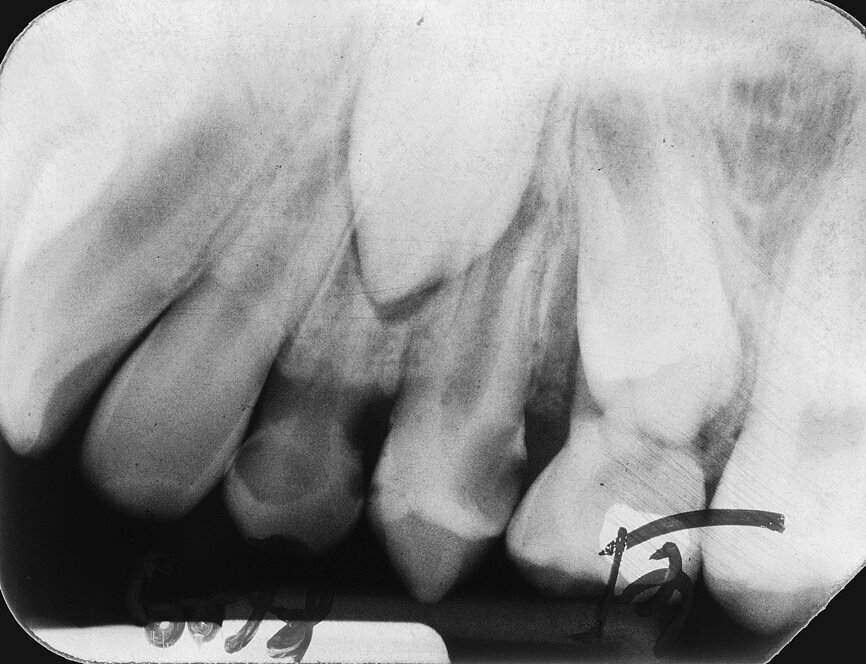

Case 1: Male (born 5 June 1987): Tooth 35

Fig. 3c: 6 May 2005 status